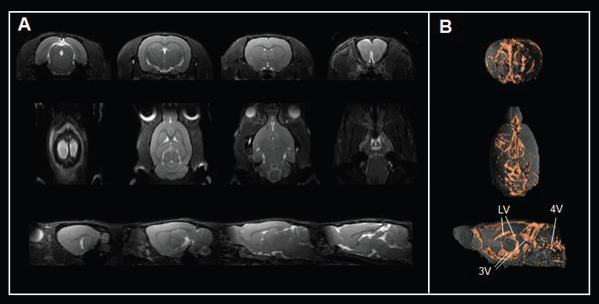

For instance, a true fast imaging with steady-state precession (TrueFISP) sequence gives contrast for cerebrospinal fluid spaces (Fig. 5A) and 3D renderings (Fig. 5B) and allows the assessment of ventricle anatomy and morphology, an important compartment for cerebrospinal fluid production and transport.

Disrupted ventricles are observed in multiple congenital neurological conditions and in response to neuronal injury or degeneration. Contrast-enhanced, flow and diffusion MRI approaches enable the monitoring of interstitial and cerebrospinal fluid flow through various extracellular compartments in the brain and spinal cord.

Multiple neurological conditions carry changes in the magnitude and direction of cerebrospinal fluid flow that are linked with disrupted waste removal and an accumulation of metabolites (e.g., lactate, ß-amyloid) alongside the trafficking of immune cells. Furthermore, assessing neurofluid flow patterns with MRI can help evaluate whether therapies can restore the normal passage of fluids.

Figure 5. Assessing brain ventricles. A) Axial, coronal, and sagittal T2-weighted TrueFISP images and B) corresponding renderings reveal the cerebrospinal fluid spaces in the rat brain. Rat brain data was acquired with a BioSpec Maxwell 94/17 using a volume coil for transmission and a phased-array coil for reception. Tissues were segmented and rendered using PMOD. LV = lateral ventricle; 3V = third ventricle; 4V = forth ventricle. Image Credit: Bruker BioSpin Group